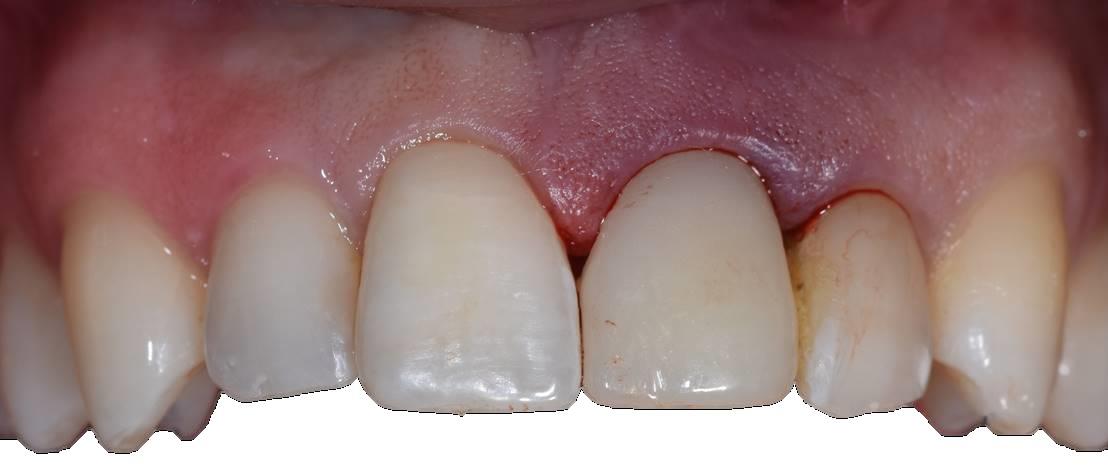

Previa impronta ottica, veniva preparato un Maryland provvisorio di adeguata forma (Figura 4) applicato sul gruppo frontale dopo estrazione atraumatica dell’elemento (Figura 5).

Il provvisorio, di forma ovoidale della parte intra-alveolare, sigillava senza compressione l’alveolo, penetrando in esso per circa 3 mm (Figura 6) (14). Prima della sua applicazione, l’alveolo veniva liberato dal tessuto granulomatoso e riempito con spugna di collagene. Nessun innesto veniva applicato nell’alveolo (15).

Il sito veniva nuovamente sigillato con il ripristino del Maryland. Il basso valore di torque implantare sconsigliava l’inserimento di un provvisorio immediato (16).

Il provvisorio veniva lasciato a dimora per altri due mesi per consentire la stabilizzazione dei tessuti e del loro profilo per poi procedere con il restauro finale in zirconio-ceramica (Figura 12).

A distanza di sei mesi dall'applicazione del restauro definitivo i tessuti apparivano stabili, con mantenimento della morfologia pre-terapia (Figura 13).